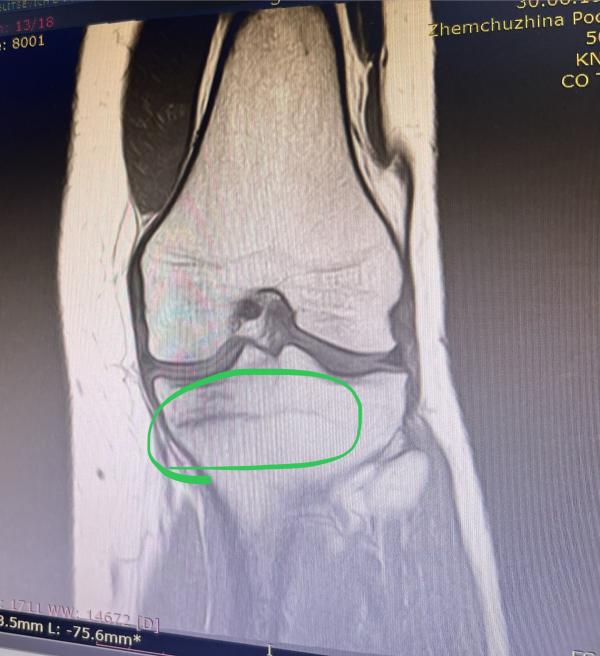

Стресс-перелом медиального мыщелка берцовой кости.

Запретили даже наступать. Так как трещина в кости не маленькая. На фото только одна проекция